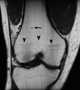

Multiple enchondromas

An enchondroma is a benign cartilage tumour found inside bones. Typically, enchondroma is discovered on an X-ray scan. [Source: Wikipedia ]